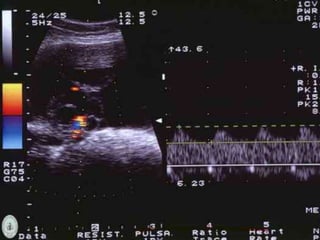

Imagenología

 Flujometría doppler: Proyecciones papilares,

neovascularización.

Imagenología  Ecografía  Tumoresmalignos: Multiloculados, sólidos ó ecogénicos, mayores de 5cm, tabiques gruesos con áreas de nodularidad.  Flujometría doppler: Proyecciones papilares, neovascularización.  USG abdominal de difícil interpretación en pacientes con enfermedad avanzada o masas tumorales grandes.  Ascitis. Schorge JO, Schaffer JI, Halvorson LM, Hoffman BL, Bradshaw KD, Cunningham G. “Cáncer ovárico epitelial”. En: Schorge JO, Schaffer JI, Halvorson LM, Hoffman BL, Bradshaw KD, Cunningham G. Williams de Ginecología. México: McGraw.-Hill; 2009. Pp. 716-737.

• #28 Cistoadenocarcinoma seroso con neovascularización.